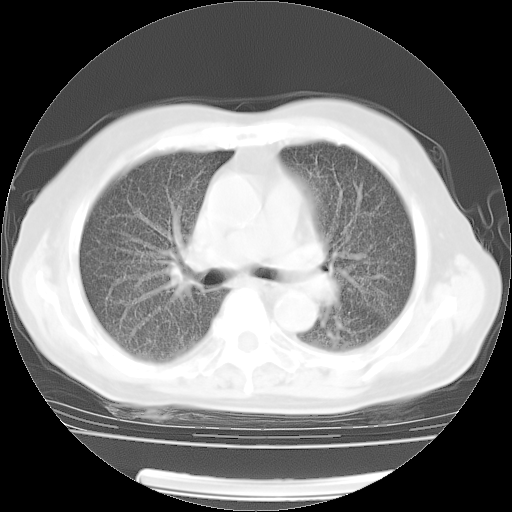

4月14日肺部CT

肺部CT平扫未见异常。